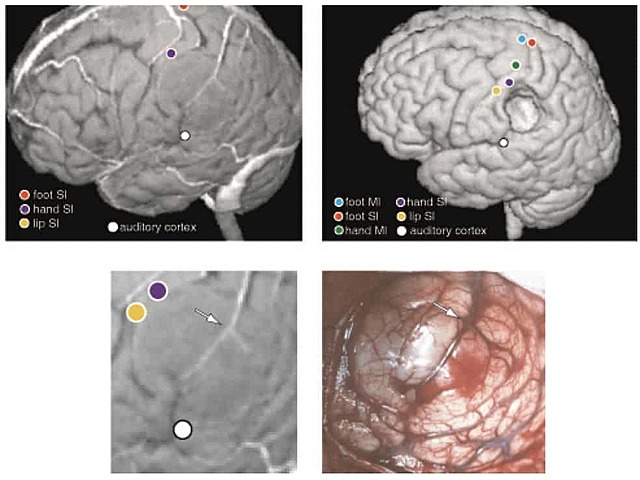

Primer caso de integración directa de la

información de la resonancia magnética funcional y la tomografía por emisión de positrones a la

neuronavegación craneal